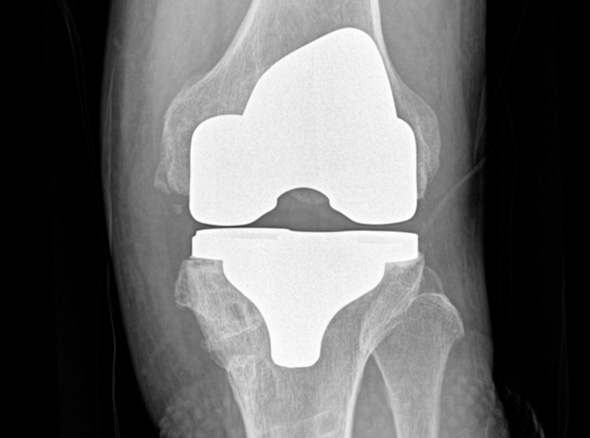

세계적인 의료기기 기업 스트라이커(Stryker)사의 특화된 임플란트를 사용합니다.

정밀한 설계, 내구성, 생체 적합성 등의 장점을 두루 갖추어 전 세계적으로 가장 많이 사용되고 있습니다.